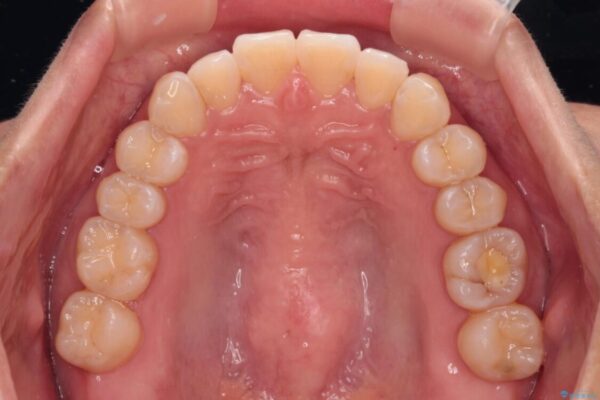

前歯のデコボコで前方に出ていることを気にして来院された患者様です。

上顎前歯が捻れて前方に飛び出しており、下顎前歯もそれに沿うようにデコボコとなっていました。

IPR(歯と歯の間を削る処置)によりスペースを獲得して上下顎前歯のデコボコを改善し、飛び出している前歯が引っ込むように設定し、インビザラインにて矯正治療を行うこととしました。

• 【モニター】前歯のデコボコをインビザラインで改善 治療前画像